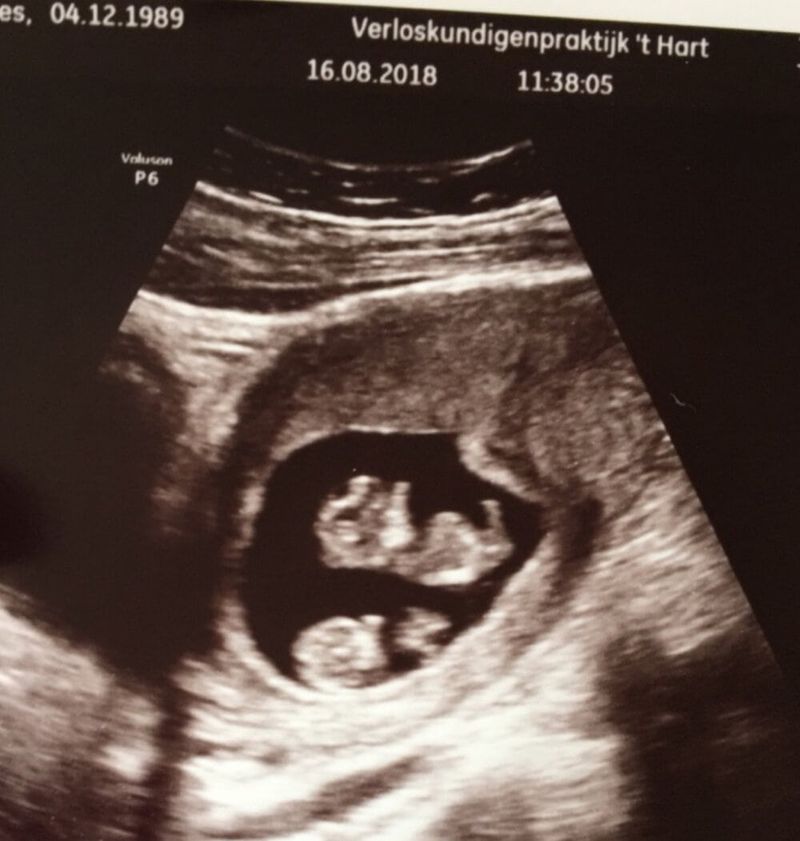

Na twee weken mochten we weer komen om te kijken hoe de kindjes waren gegroeid. Gelukkig ging dit goed. Wel werden we overdragen naar het ziekenhuis. We meldden ons op 22 augustus voor de eerste controle. We waren nieuwsgierig of de kindjes eeneiige of twee-eiige waren. De kindjes deden het goed en de gynaecoloog vertelde ons dat we een eeneiige tweeling met allebei een eigen vruchtzak hadden. Dit is de gunstigste variant, waar desondanks helaas nog wel een aantal risico’s bij horen. Door deze risico’s worden de kindjes elke twee weken gecheckt op TTTS en TAPS.